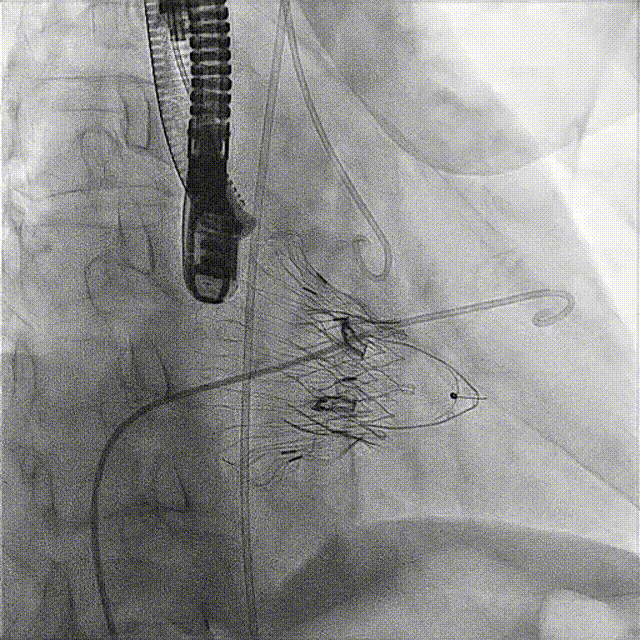

術后DSA

術前經過全面系統的評估后,考慮患者存在高齡、心功能減低、三尖瓣瓣環重度擴張(三尖瓣極重度反流)等高危因素,因此廈心結構心團隊聯合超聲心動、麻醉及護理團隊,制定了詳盡的圍術期治療方案及術中治療難點預案。術中,由王焱院長主刀,在蘇茂龍主任超聲心動團隊的輔助,上海市第一人民醫院陸方林主任的協助下,僅用時30分鐘,即順利完成了三尖瓣原位置換的手術。術中患者血流動力學穩定,術后即刻顯示LuX-Valve Plus瓣膜位置良好,固定穩定,瓣膜功能正常,無瓣周漏。